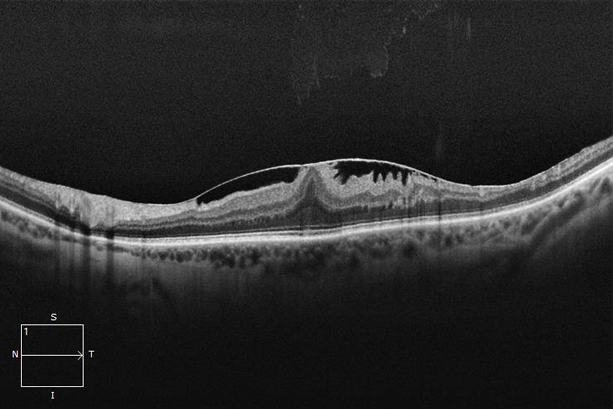

Macular Hole

A small break in the macula that can cause blurred or distorted central vision. Surgical repair can restore sharpness

Epiretinal Membrane

Scar tissue that forms on the surface of the retina, leading to vision distortion and blurriness. Surgery can help restore clarity.